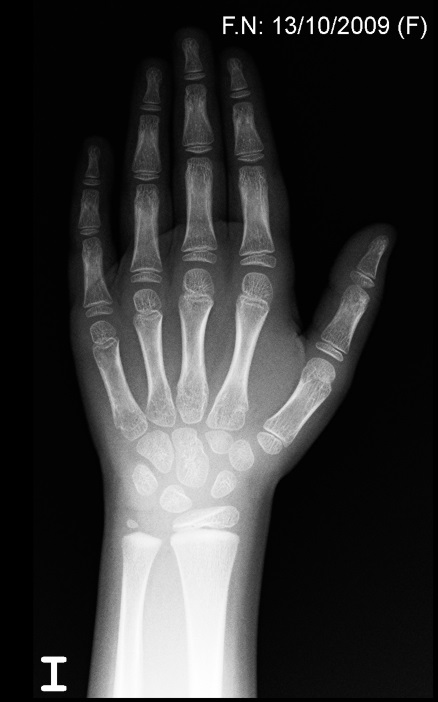

• Rx de muñeca izquierda: edad ósea de siete años (recordemos que la edad cronológica es de cinco años y diez meses).